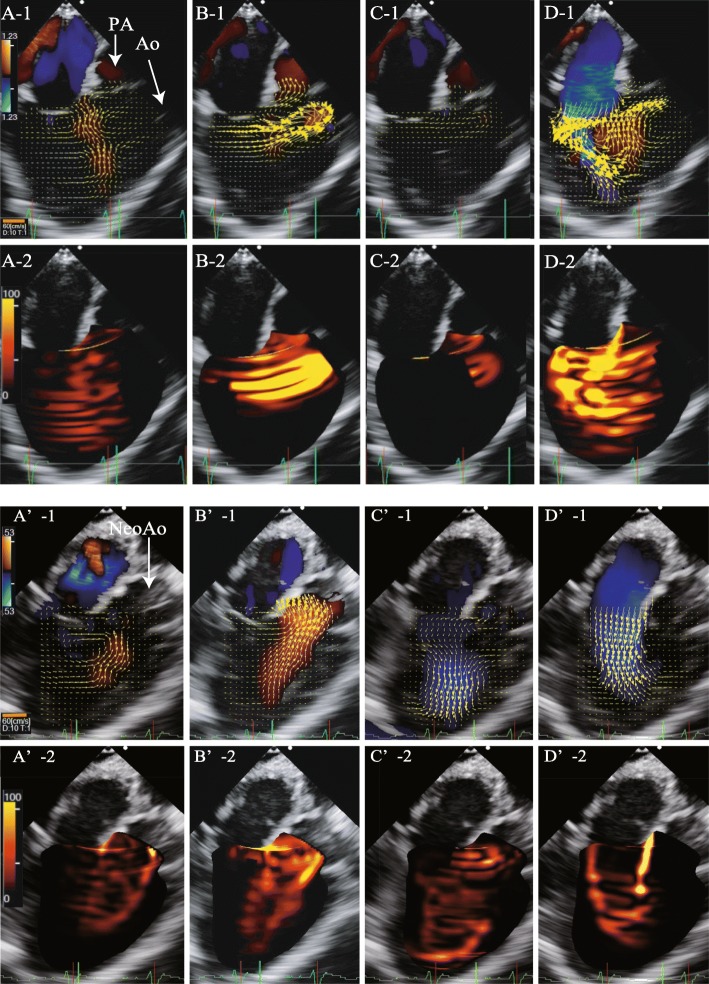

We performed Glenn, DKS, and atrial septal defect enlargement procedures. Pre- and post-CPB hemodynamic parameters are shown in Table 1. Figure 2 shows the pre- and post-CPB VFM images analyzed by TEE, and Fig. 3 shows the pre- and post-CPB chart of EL, and KE values during one cardiac cycle. Furthermore, Additional file 1: Movie S1 and Additional file 2: Movie S2 show the pre-CPB VFM and EL and Additional file 3: Movie S3 and Additional file 4: Movie S4 show the post-CPB VFM and EL in the mid-esophageal long-axis views by TEE, respectively. After the surgery, the mean EL and mean KE decreased from 39.8 to 14.5 mW/m and from 49.7 to 46.5 mW/m, respectively. EPI increased from 1.25 to 3.20. Consequently, the patient was moved to the general ward 23 days after the initial surgery, without any inotropic support.

Fig. 2.

Vector flow mapping by transesophageal echocardiography. Vector flow mapping (VFM) of the mid-esophageal long-axis view before (A–D) and after (A'–D') cardiopulmonary bypass. Brightness indicates high energy loss. After the surgery, EL decreased dramatically, especially in the diastolic phase. A,A’:isovolumic contraction phase. B,B’:systolic phase. C,C’:isovolumic relaxation phase. D,D’:Diastolic phase. -1: vector flow mapping image, orange line is scale bar of the vector. -2: Energy loss image. Abbreviations: Ao, aorta; EL, energy loss; Neo Ao, neo aorta; PA, pulmonary artery